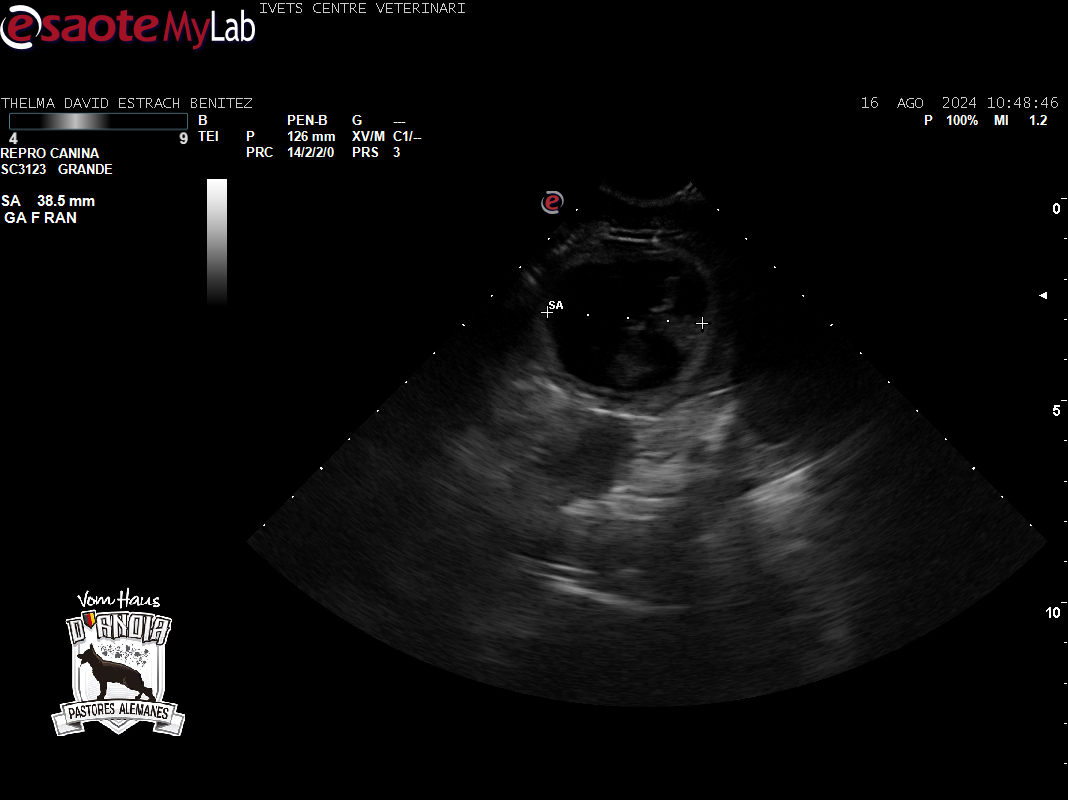

Ayer Viernes 16/08/2024 hicimos la segunda ecografía de control de gestación a Thelma (Turca de Usurbe), para ver cómo vá nuestra próxima Camada F de Pastores Alemanes de linea de Trabajo 100% DDR Puro

Parece ser que la futura mamá lleva bastantes cachorros, y lo más importante, ella está perfecta.

Por lo visto en la ecografía, puede ser una Camada numerosa, algo que confirmaremos en la radiografía de fin de embarazo que hacemos sobre los 52 – 55 dias de gestación.